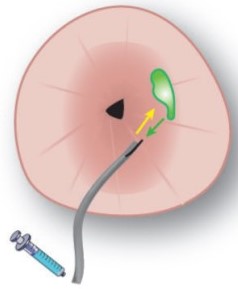

First endoscopic study

In 2014 the first study started using systemic and topical administration of a fluorescence-labelled antibody against vascular endothelial growth factor (VEGF) utilizing a NIR infrared camera system.

Topical fluorescent guided endoscopy | OMIG